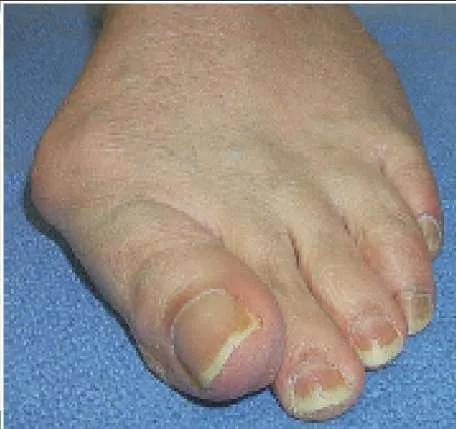

A 44-year-old woman presents with chronic pain in the region of the forefoot. She is unable to wear a shoe with a heel and she has pain in the region of the second toe. On examination, she has swelling of the second toe and painful inflammation of the metatarsophalangeal joint. A clinical picture of her foot is presented. Your initial treatment consists of:

This patient has idiopathic synovitis of the second metatarsophalangeal (MP) joint. This may be associated with hallux valgus or a long second metatarsal, leading to attritional changes in the volar plate and secondary instability of the MP joint. Immobilization of the toe with limitation of dorsiflexion is required. Although cortisone injection may be effective, toe support must be the initial form of treatment.